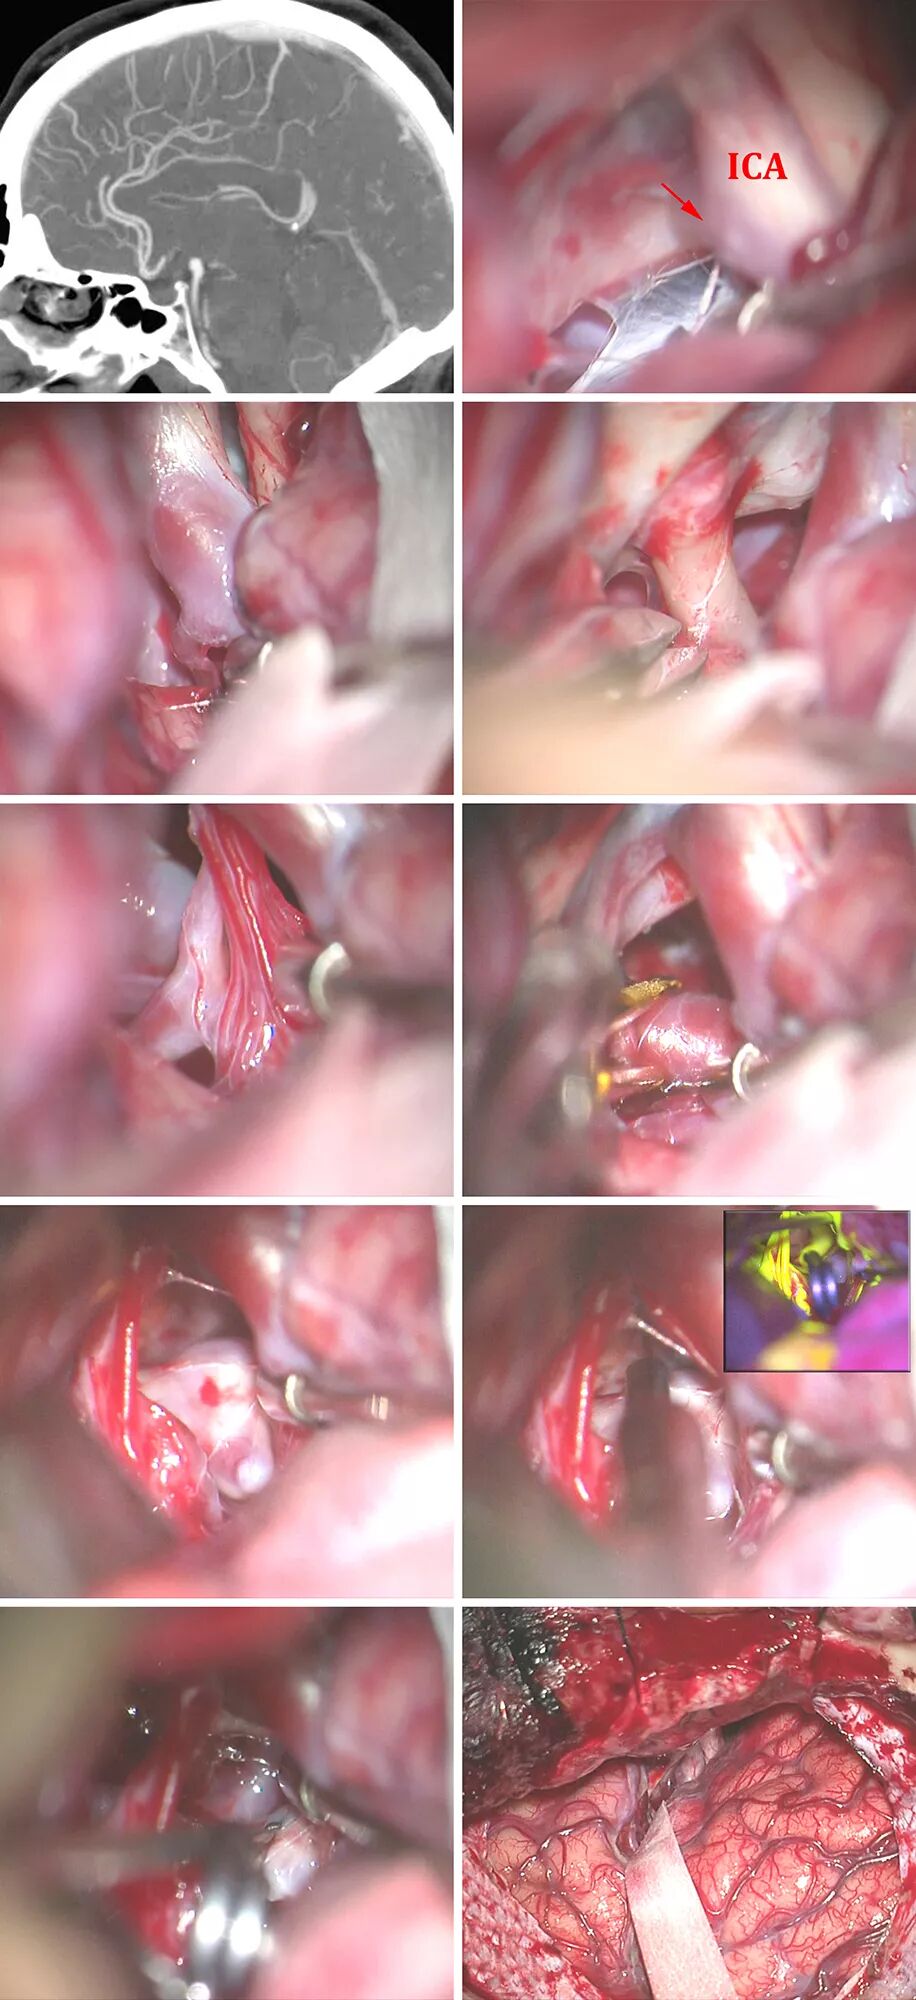

图13:左侧经侧裂入路显露一个基底动脉分叉部动脉瘤(显示Liliequist膜与PCoA起始处(箭头))(第一排)。通过Liliequist膜找到PCoA,将动眼神经从蛛网膜附着带上松解(第二排)。轻柔推移PCoA的丘脑穿支血管,安全地从近端控制基底动脉(第三排)。直形永久夹放置到瘤颈后,立刻用固定牵开器牵拉颞叶(第四排)。仔细探查发现对侧P1段起始处及相关的穿支保留完好。动态牵拉使皮质的损伤最小(下排)。

注:ICA:颈内动脉。